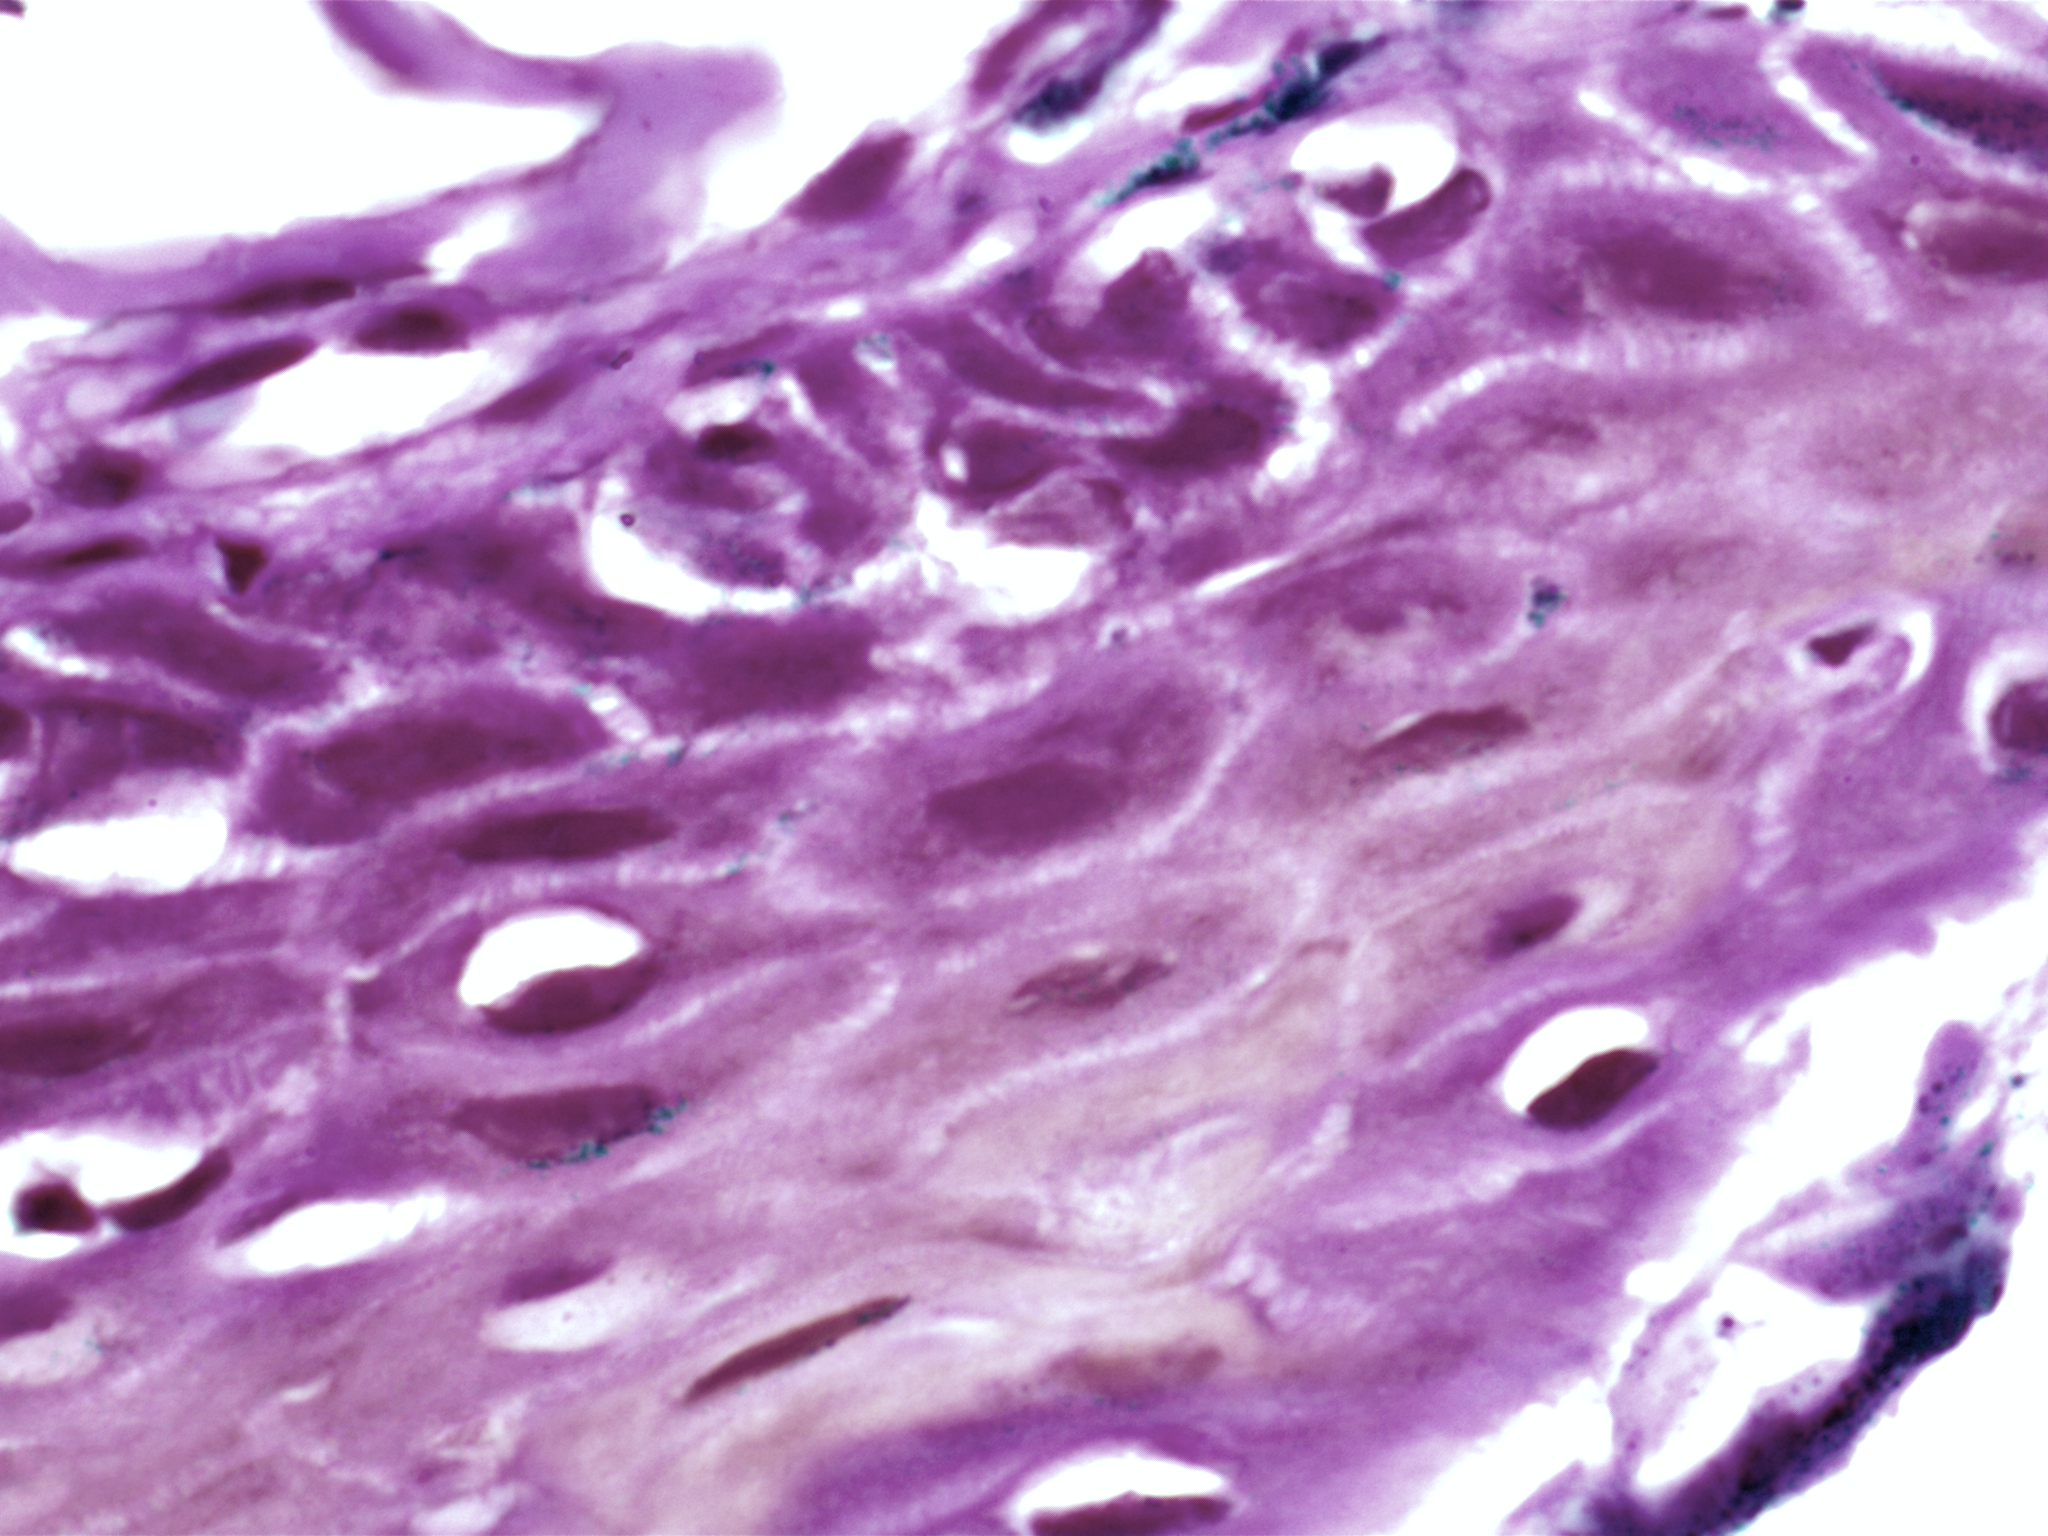

| Description: | Oral cancer is a global health challenge with a difficult histopathological diagnosis. The accurate histopathological interpretation of oral cancer tissue samples remains difficult. However, early diagnosis is very challenging due to a lack of experienced pathologists and inter- observer variability in diagnosis. The application of artificial intelligence (deep learning algorithms) for oral cancer histology images is very promising for rapid diagnosis. However, it requires a quality annotated dataset to build AI models. We present ORCHID (ORal Cancer Histology Image Database), a specialized database generated to advance research in AI-based histology image analytics of oral cancer and precancer. The ORCHID database is an extensive multicenter collection of high-resolution images captured at 1000X effective magnification (100X objective lens), encapsulating various oral cancer and precancer categories, such as oral submucous fibrosis (OSMF) and oral squamous cell carcinoma (OSCC). Additionally, it also contains grade-level sub-classifications for OSCC, such as well- differentiated (WD), moderately-differentiated (MD), and poorly-differentiated (PD). The database seeks to aid in developing innovative artificial intelligence-based rapid diagnostics for OSMF and OSCC, along with subtypes. |

| Summary: | The number of images available in each of the five classes(folders), which are as follows, Normal, OSMF, WDOSCC, MDOSCC, and PDOSCC. Each class folder consists of subfolders representing different tissue slides collected from different patients. We have made an initial attempt to provide a comprehensive image database for two of the most prominent oral conditions, OSCC and OSMF. We believe that more such databases will be made publicly available in the near future. These comprehensive image databases will facilitate the development of accurate AI-based diagnostic tools for oral diseases, ultimately improving patient care and outcomes in the field of oral healthcare. In future, integration of databases comprising molecular markers, transcriptome, metabolome, and other biomarkers, combined with oral histological image through advanced AI-driven imaging techniques, holds great promise in improving diagnostic accuracy and precision. This potential has already been observed in the diagnosis of lung and breast cancers. This expansion will aid in developing a more comprehensive AI-driven diagnostic tool. |

| The ORCHID database is an extensive multicenter collection of high-resolution images captured at 1000X effective magnification (100X objective lens). Tissue slides were collected with the approval of an ethical committee from the participating hospitals and research institutions. The buccal mucosa tissue samples were collected for three classes, normal, OSMF, and OSCC, with grade-wise annotation from the pathologists at each hospital. Biopsy samples of normal, OSMF and OSCC tissues underwent H&E staining. The staining procedure was conducted either in-house or outsourced to different laboratories. To eliminate staining variations across different laboratories, the preparation of H&E slides involved five histopathology labs, each utilizing their own independently developed and optimized protocols for the staining process. Following staining, the samples were examined under a microscope by a skilled histopathologist to assess cellular morphology, and tissue architecture, and identify any distinctive features or abnormalities specific to each sample type. This evaluation by the histopathologist involved grading the tissue slides for OSCC and OSMF, as well as differentiating between normal and diseased tissue sections. Images were acquired using a 1000X magnification (100X objective) lens from Leedz microimaging (LMI) bright field microscopy. To capture the images consistently, we utilized ToupView imaging software, which was configured for automatic adjustments. This setting applies to both white balance and camera settings, thereby standardizing the image acquisition process across different slides. The images of the H&E stained slides were captured at 1000X magnification(100X objective lens). By setting the ToupView software to automatically adjust white balance and camera settings, we aimed to minimize human intervention and the variability it introduces. This approach ensures that the images are not only consistent but also replicable in different laboratory settings, provided similar equipment and software settings are used. We collected approximately 100–150 images per tissue slide, which were stored in PNG file format. |